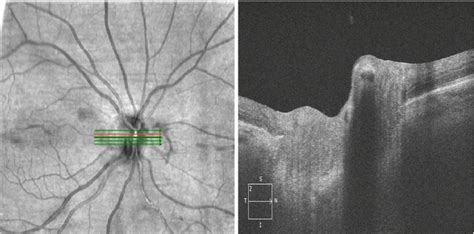

Retinal Arterial Occlusion - Andrea Cusumano